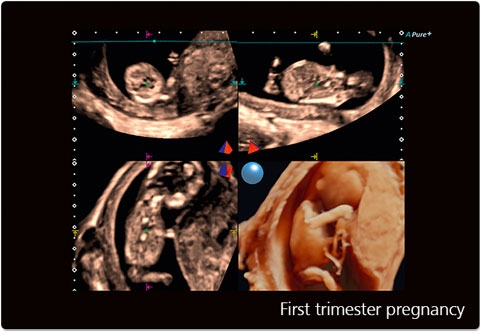

Режимы визуализации Canon (Toshiba) Aplio 300

B, M, PWD, CWD, ЦДК, THI, 4D, динамический поток (Dynamic Flow), энергетический доплер (Power), контрастная эхография (CHI 2D) и комбинированные режимы, включая следующие: B/M, B/PWD, BDF/PDW, BDF/MDF,BDF/MDF/PWD, 2D/CWD, BDF/CWD (BDF-режим изображения, в котором CFM изображение накладывается на B-режим изображения, MDF-режим изображения, в котором CFM изображение накладывается на M-режим изображения)

• ApliPure - технология повышения качества изображения

• STIC - исследование сердца плода в режиме объёмной визуализации

• 3D Color - цветное 3-х мерное изображение

• STIC Color - цветная объёмная визуализация сердца плода

• MPR - функция мультипланарной реконструкции для визуализации исследуемой области в 3-х ортогональных плоскостях

• FlyThru - функция виртуального перемещения по полым структурам, например, сосудам

• Трехмерная эхография в реальном времени с использованием специализированных 4D датчиков;

• Программа анализа сердца плода в трех проекциях в реальном времени 4D Stick;